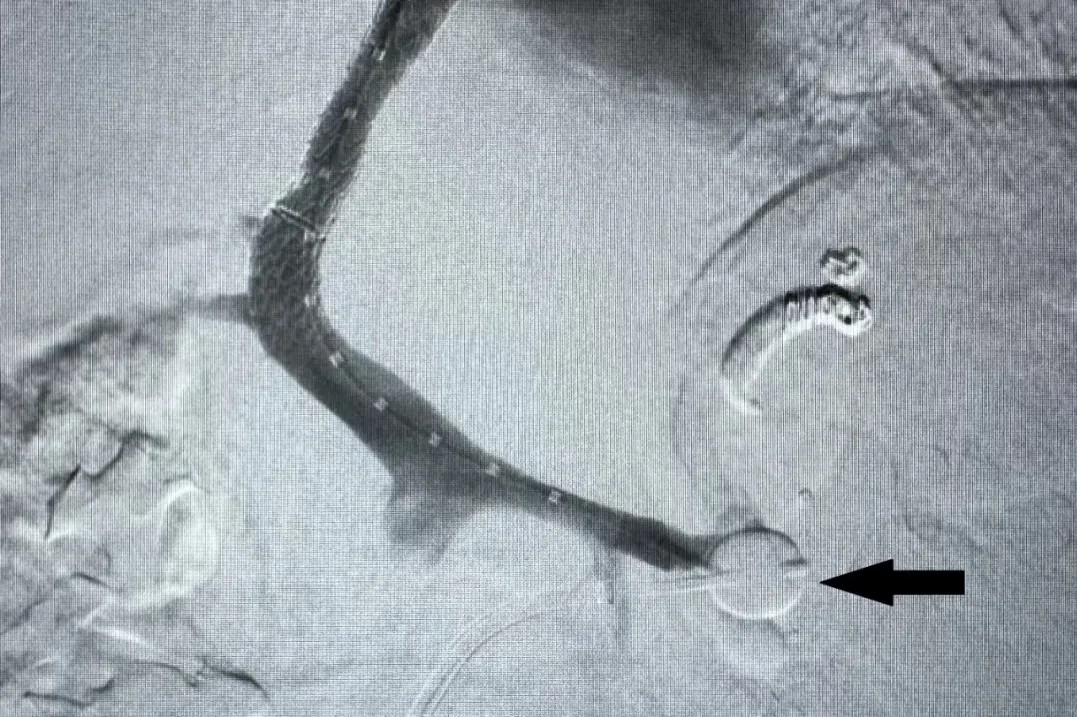

成功行TIPS分流及脾肾分流道堵塞(黑色箭头)